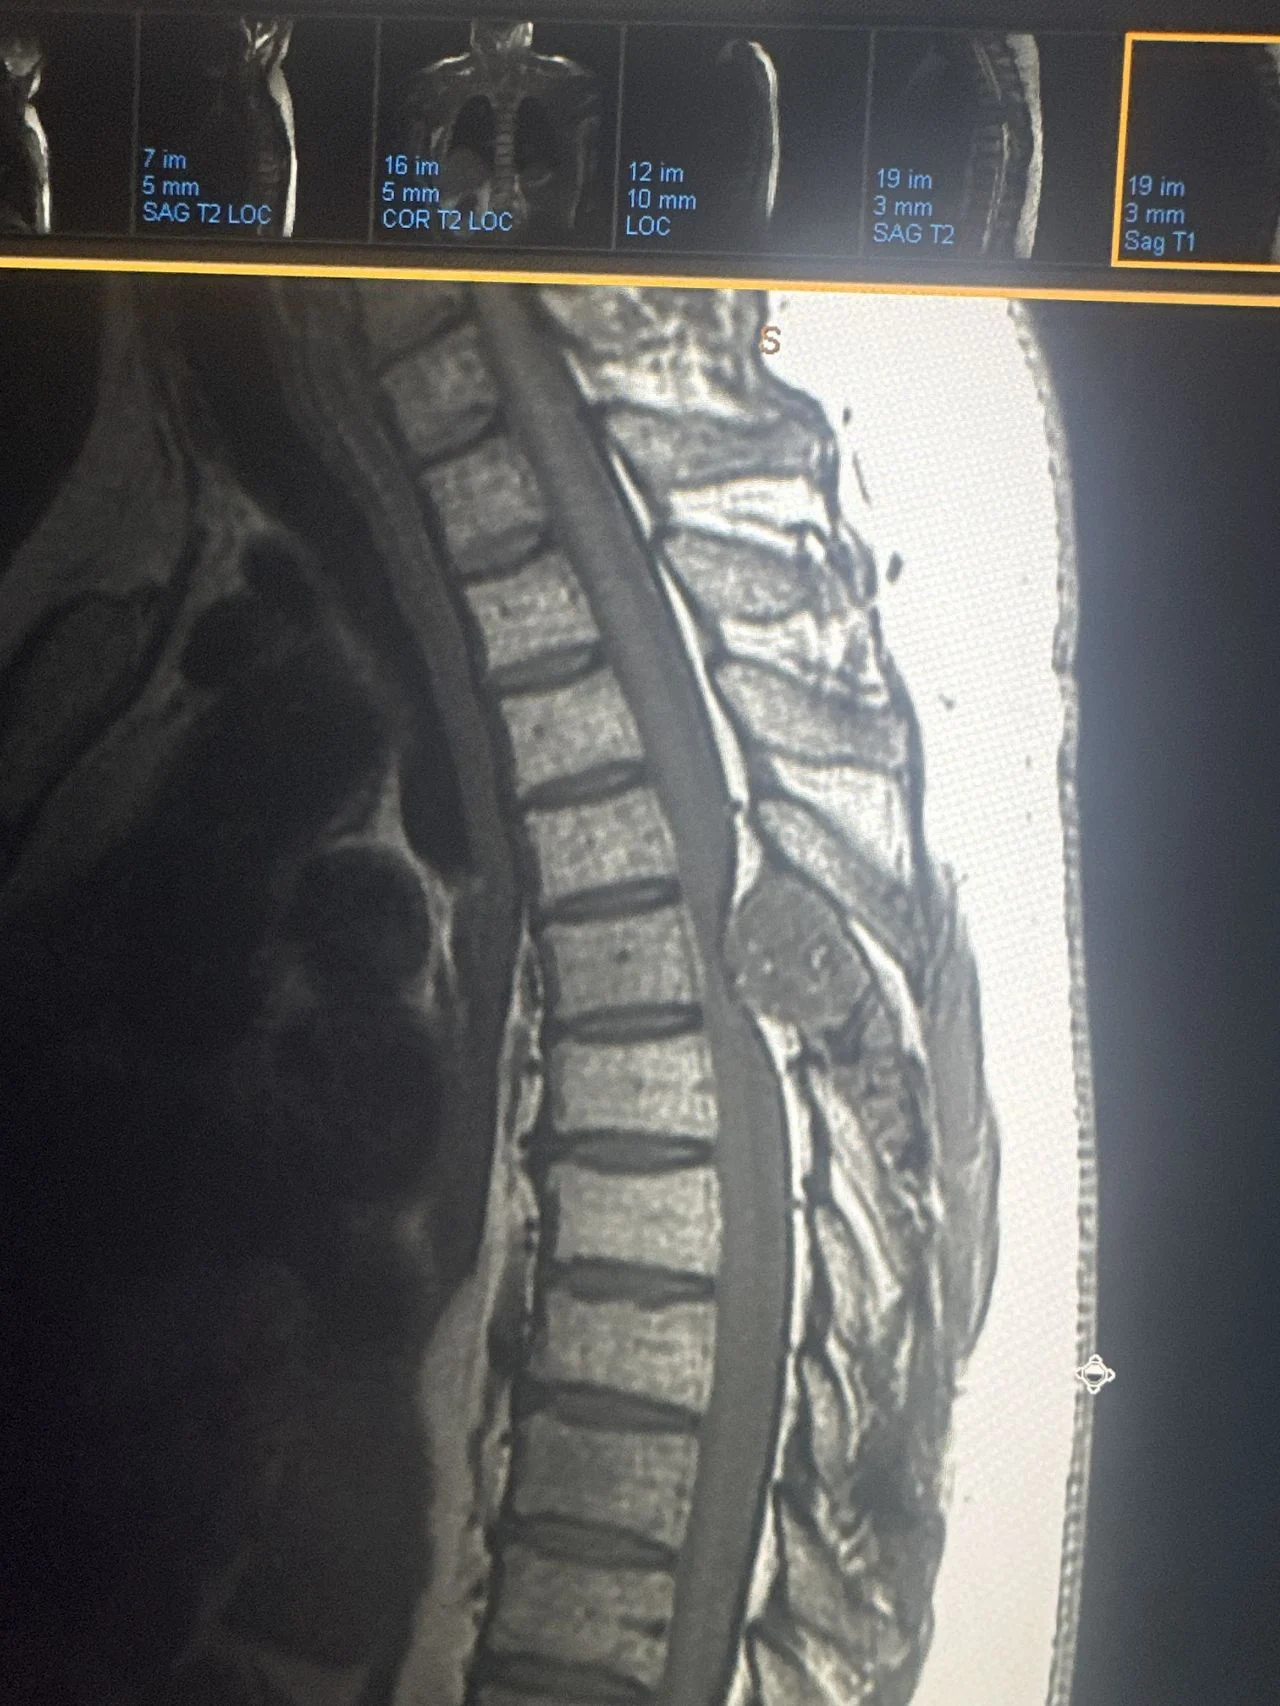

After consulting with an orthopedic surgeon colleague at 10:30 PM, we both agreed: this needed urgent attention. I insisted Chip get imaging done immediately when he returned to Florida. Within days, scans revealed multiple bone lesions—stage 4 kidney cancer recurrence.